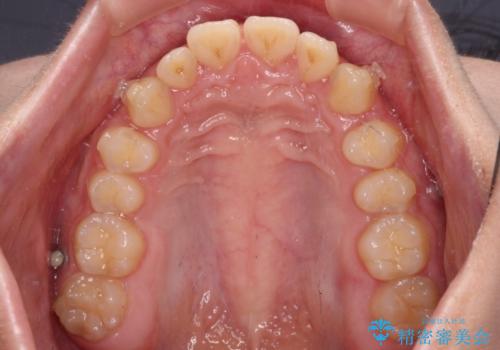

- 深い咬み合わせと上顎前歯の突出感を気にして来院された患者様です。

当院では通常、臼歯の咬合が理想的な位置に対して上顎が前方位にある場合。ワイヤー矯正または補助装置の併用したインビザライン矯正を選択しています。

今回は、できるところまででいいのでインビザライン単体で治療をしたいという希望があったため、インビザラインにて矯正治療を行うこととしました。

正面や横からの写真ではきれいに治っており、患者様は大変満足のいく仕上がりとなりましたが、深い咬み合わせの改善は不十分で、奥歯の咬み合わせも改善させることができませんでした。

インビザラインは、咬合力の強い方ですと、奥歯が歯肉内にめり込んでしまうため、前歯が強く接触してしまうことがあります。

こちらの方は、奥歯はしっかりと噛んだのですが、歯肉にめり込んでしまったことで、歯肉が腫れやすくなってしまいました。